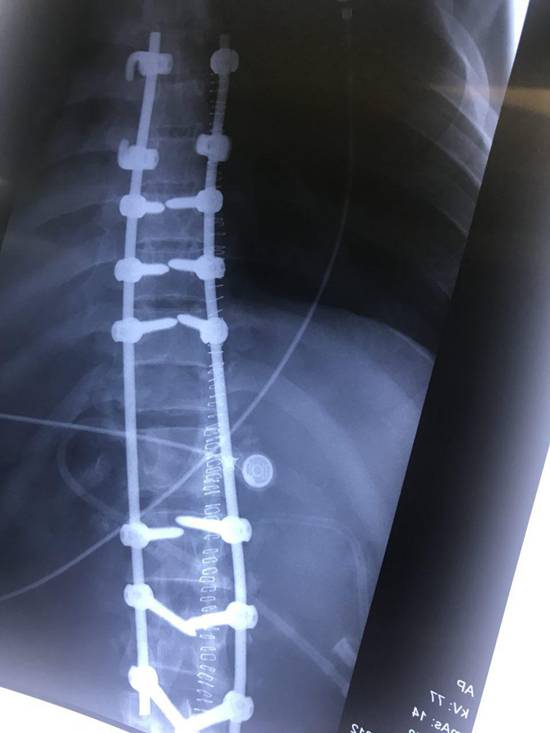

بيمار آقاى 28 ساله در تاريخ 20 آبان 96 در حين خدمت به زائرين محترم امام حسين در كربلاي معلي از ارتفاع نسبتاً زياد روي داربستهاي آهنين سقوط كرده و دچار صدمات شديد مغز و ستون فقرات شد كه عمده ضايعات آن شكستگي وسيع جمجه، كنتوزيون مغزي، كما، شكستگي و در رفتگي مهره 12 پشتي و اول كمري (L1/T12) بود. به علت گسيختگي ستون فقرات بيمار قابل انتقال به ايران نبوده و بلافاصله به بخش ICU بيمارستان امام زين العابدين در كربلا منتقل گرديد. مسئول مربوطه طي تماس با بيمارستان بهمن درخواست اعزام تيم پزشكي به كربلا را نمودند.

تيم پزشكي جناب آقاي دكتر سيد مصطفي سادات،جراح ستون فقرات، به همراه يكي از همكاران زبده خود جناب آقاي دكتر احمدرضا ريحاني و دو تكنسين ورزيده اطاق عمل در كمتر از 24 ساعت با همراه داشتن ست هاي جراحي كامل جهت تثبيت بي ثباتي ستون فقرات و بررسي وضع نخاعي بيمار به كربلا اعزام شدند. بيمار در روز پنجشنبه 25 آبان ماه در اتاق عمل بيمارستان امام زين العابدين كربلا جراحي گرديد كه حدود 4 ساعت به طول انجاميد. در حال حاضر پس از گذشت حدود يك هفته از جراحي وضع هوشياري بيمار بنا به گفته تيم معالج حاضر در كربلا رو به بهبودي مي باشد.